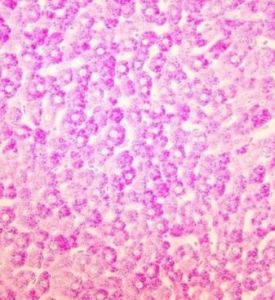

正常情況下,紅細胞系統的原、幼紅細胞和成熟紅細胞;粒細胞系統的原粒細胞、原單核細胞和大多數淋巴細胞為陰性反應。自早幼粒階段以後的粒細胞和幼單核細胞可呈弱陽性反應。

(1)急性淋巴細胞白血病、淋巴組織惡性增生性疾病、紅白血病、戈謝病的原始細胞呈強陽性反應或陽性反應;缺鐵性貧血、珠蛋白生成障礙、骨髓增生異常綜合徵亦可呈陽性反應;急性粒細胞白血病、急性單核細胞白血病、良性淋巴細胞增多症、尼曼-皮克細胞呈陰性反應或弱陽性反應。巨幼細胞性貧血、溶血性貧血、再生障礙性貧血等,幼紅細胞為陰性反應。偶有個別幼紅細胞呈陽性反應。

(2)幫助鑑別不典型巨核細胞和霍奇金細胞,巨核細胞呈強陽性反應;霍奇金細胞呈弱陽性或陰性反應。

(3)幫助鑑別白血病細胞和腺癌骨髓轉移的腺癌細胞,腺癌細胞呈陽性反應。